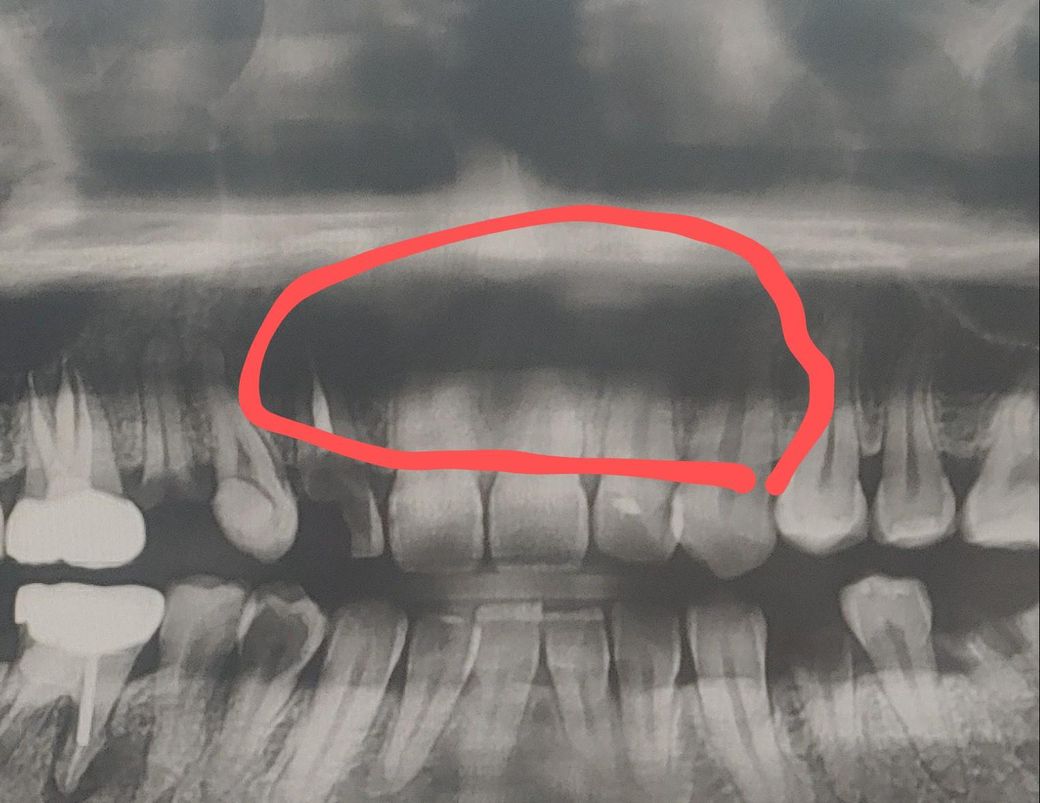

치아 파노라마 상에 앞니들 위에가 검게 보이는데 잇몸 뼈랑 뿌리가 염증때매 녹은걸까요?

치아 파노라마 상에 앞니들 위에가 검게 보이는데 잇몸 뼈랑 뿌리가 염증때매 녹은걸까요..................?

• 1번 째 사진

위쪽에 나타나는 검은 색 부분은 충치나 염증에 의해서가 아닌 조직의 밀도에 의한 차이로 인한것입니다.

저부위는 잇몸뼈가 녹은게 아니라 연조직과 겹쳐서 보이는곳 또는 콧구멍등이 겹쳐서 그렇게 보이는겁니다.

잇몸 뼈와 치근의 염증으로 인한 녹음(흡수)일 가능성도 있습니다. 치아 뿌리 주변에 염증이 생기면, 그 부위의 뼈가 흡수되어 검게 나타나게 됩니다.

보다 정확한 상태 확인읠 위해 치과에 방문하여 실제로 상태를 보면서 확인이 필요로 됩니다.